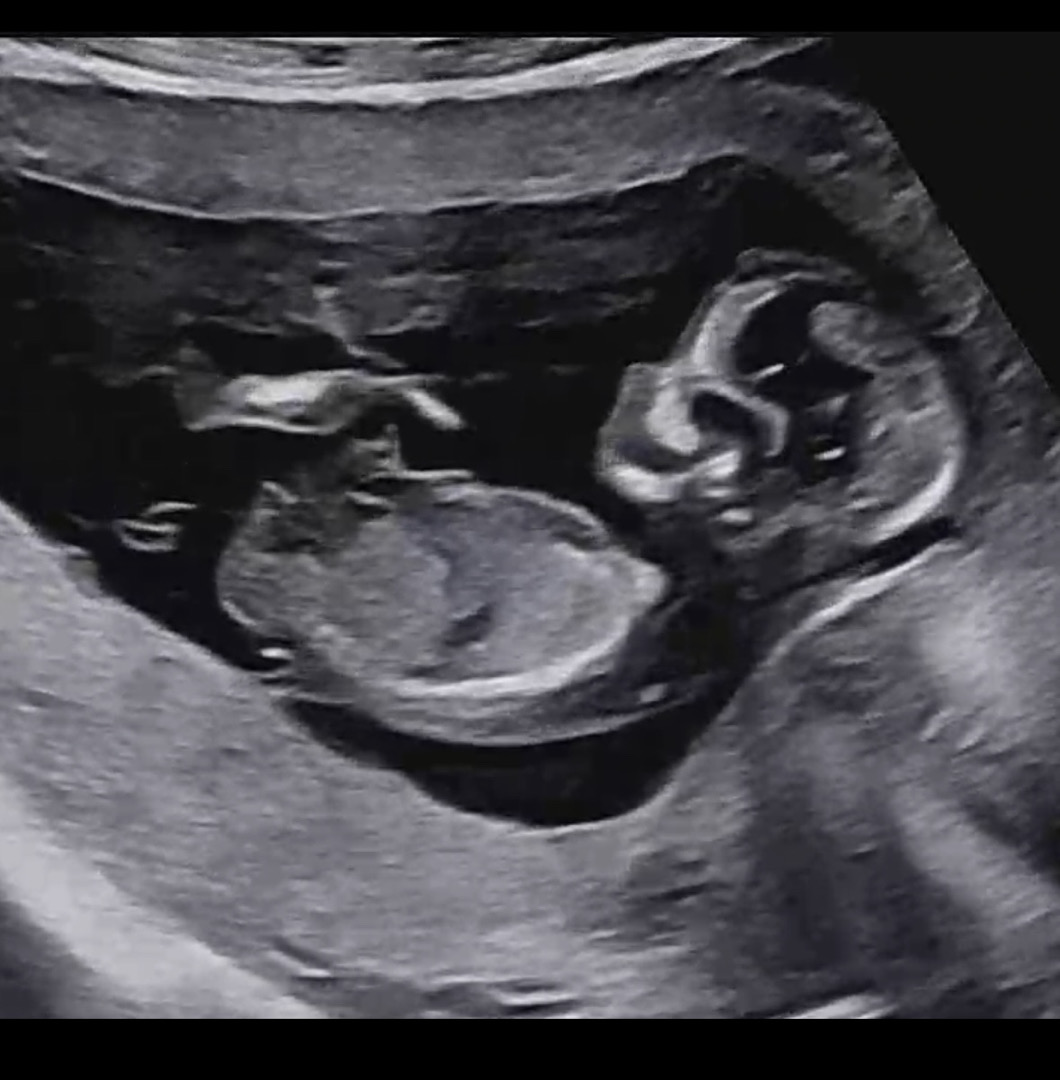

각도법 봐주실수 있나요 🥹?

12주 4일이에요 ㅎㅎ 각도법상 어때보이나요 ~???

한장 더있어용~

이사진은 딸 같아용....!